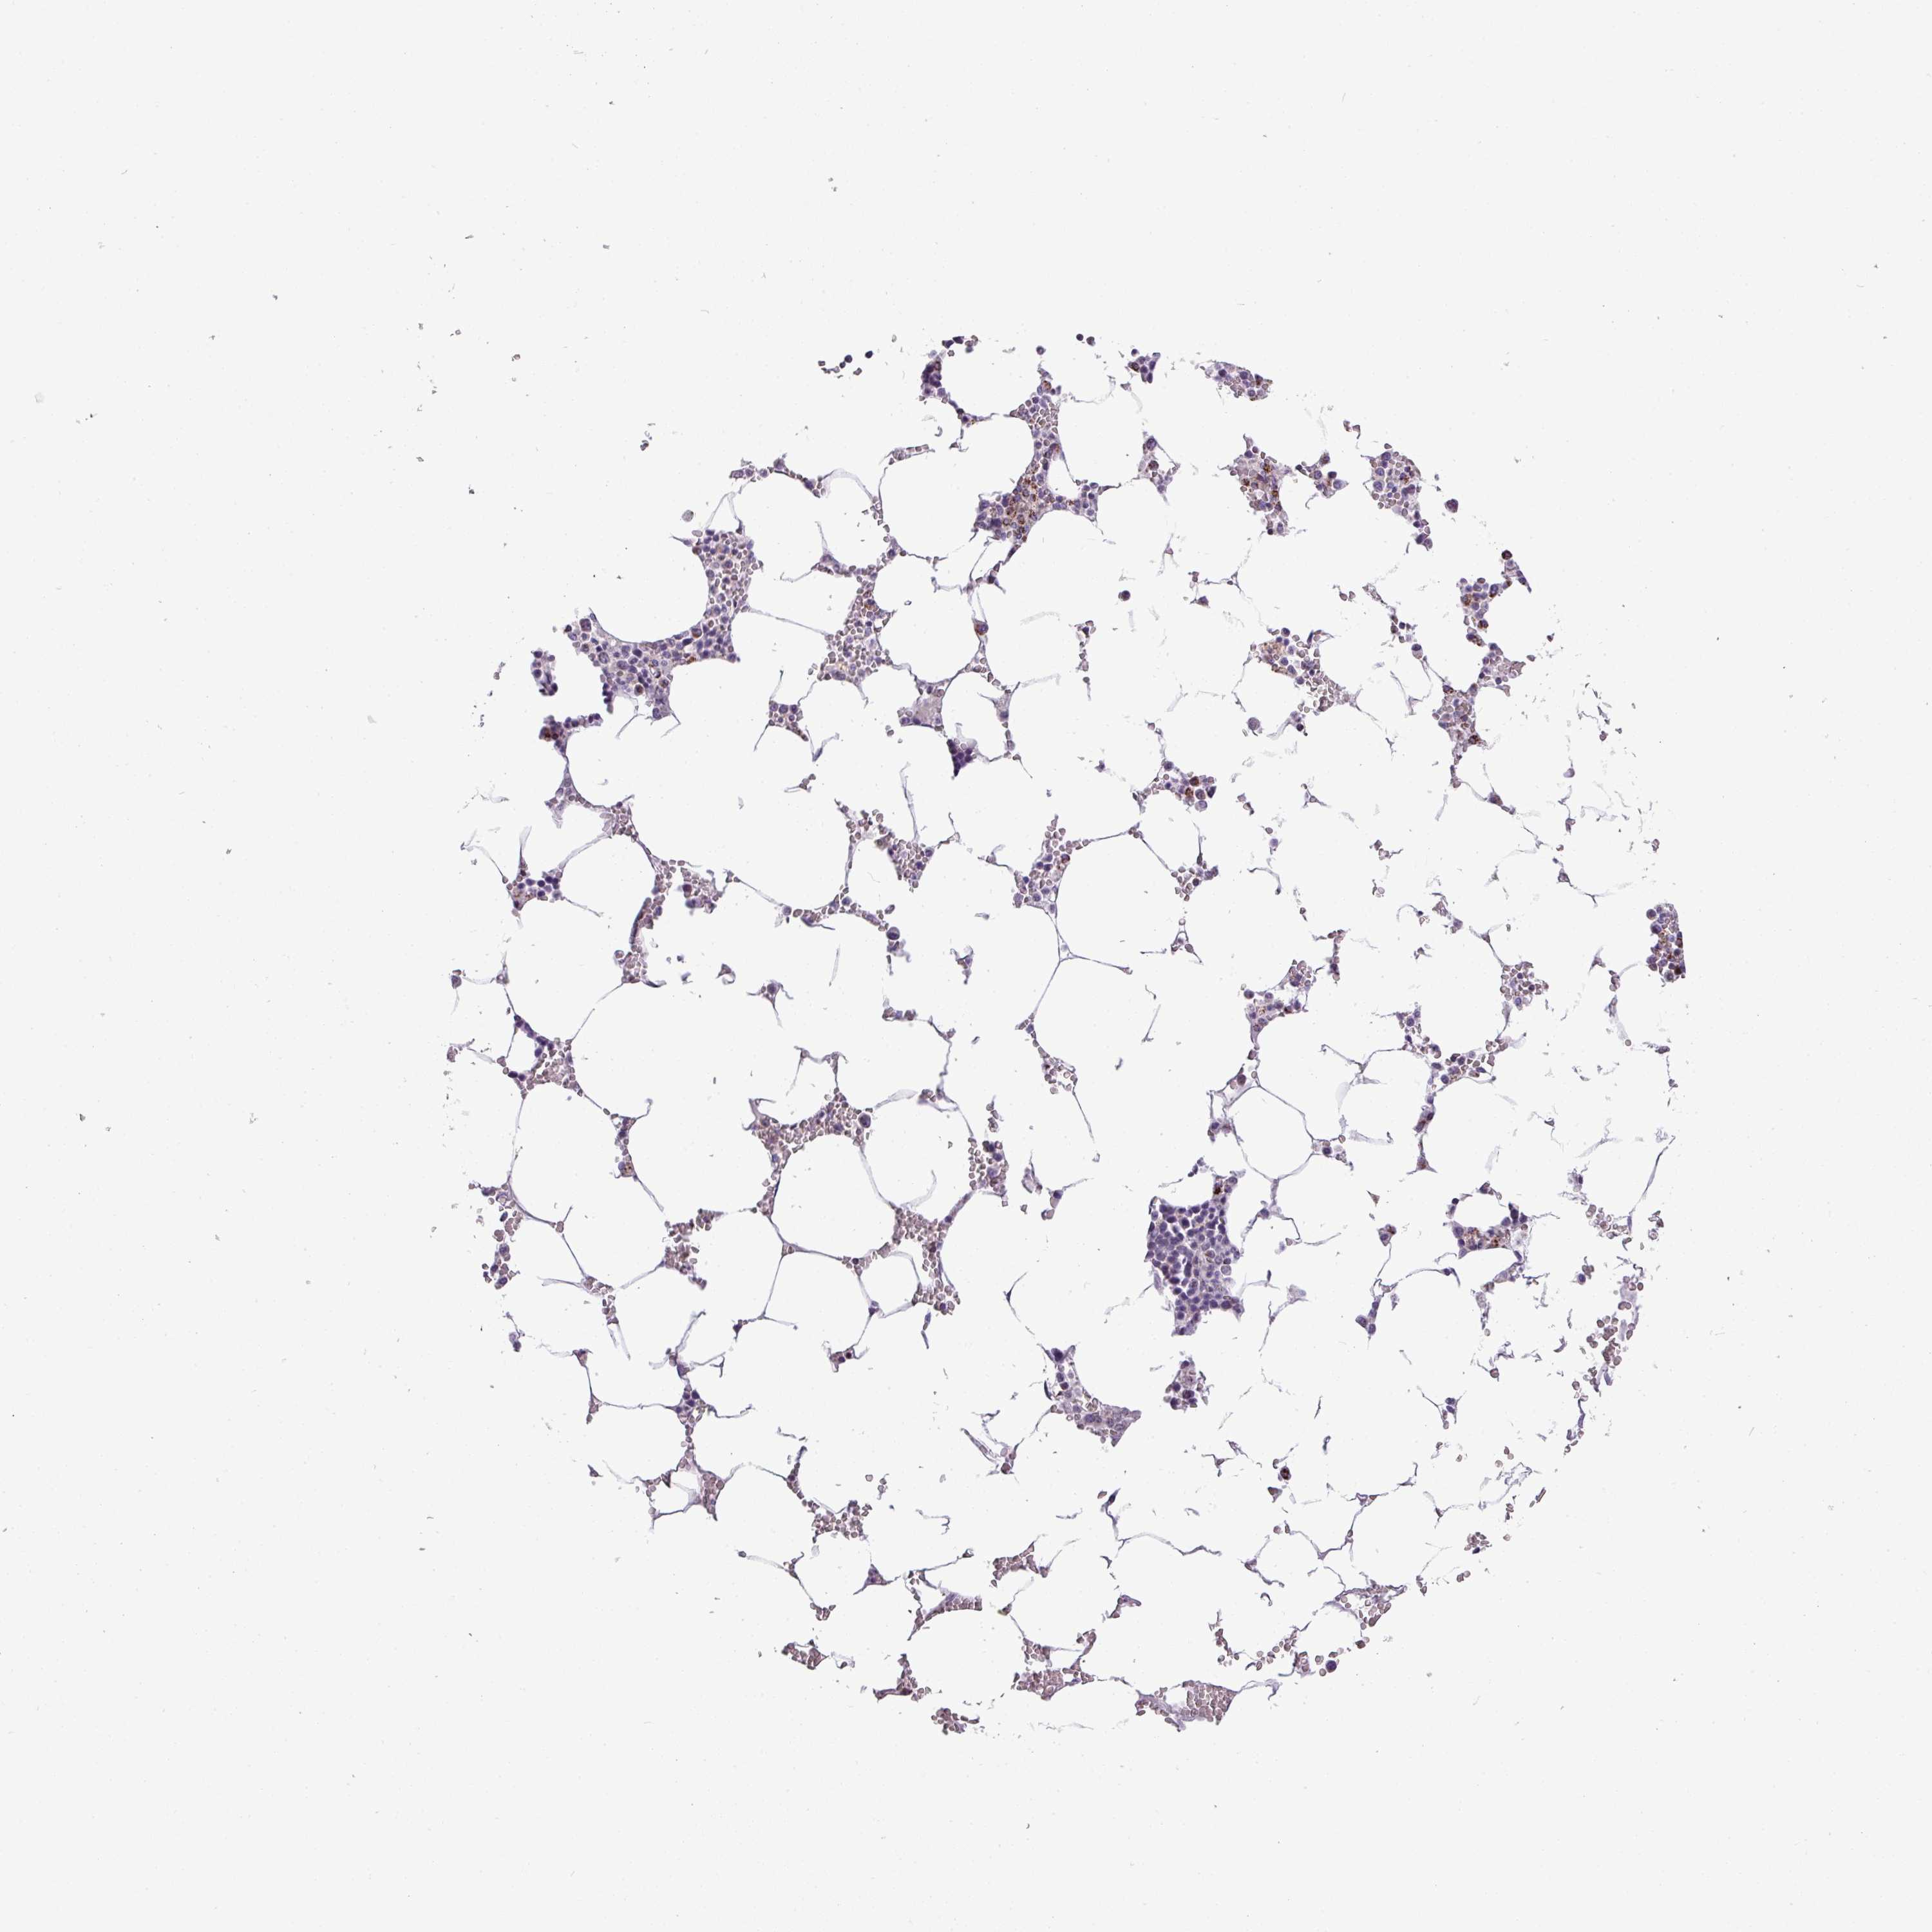

TISSUE PRIMARY DATA BONE MARROW Show tissue menu

Bone marrow

BONE MARROW - Antibody stainingi

Antibody staining in the annotated cell types in the current human tissue is reported as not detected, low, medium, or high, based on conventional immunohistochemistry profiling in selected tissues. This score is based on the combination of the staining intensity and fraction of stained cells.

Each image is clickable and will lead to virtual microscopy that enables deeper exploration of all samples and also displays staining intensity scores, fraction scores and subcellular localization as well as patient and tissue information for each sample.

Antibody HPA001689

Hematopoietic cells Not detected